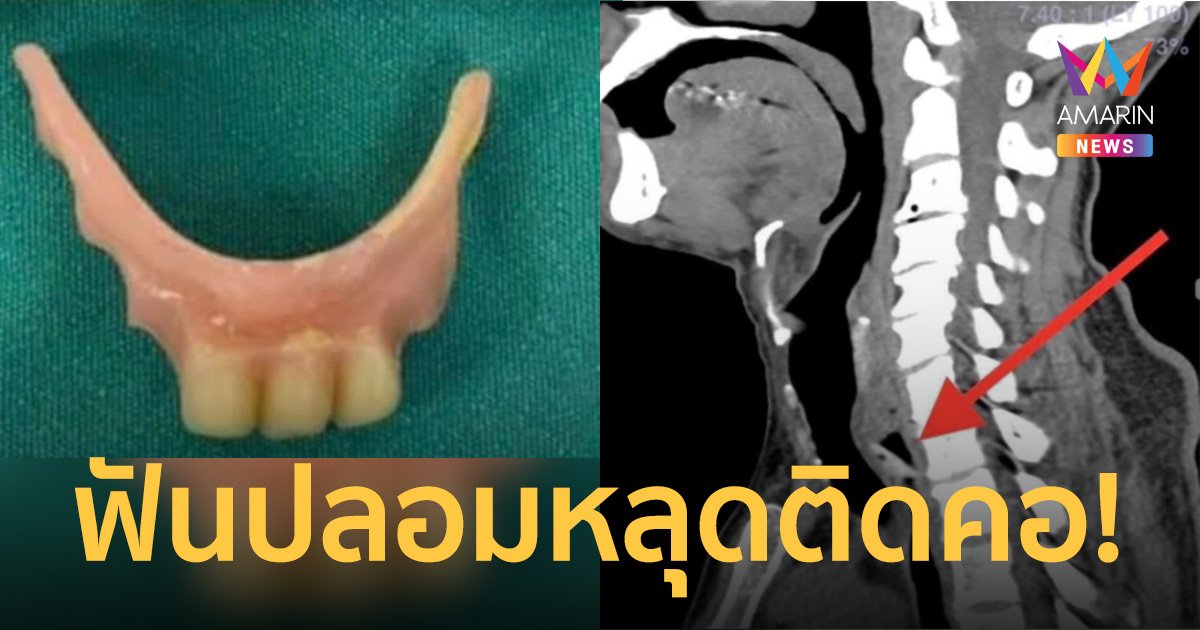

อดีตข้าราชการครูบำนาญเผยอีกว่า หลังรู้ตัวว่าฟันปลอมติดคอด้วยความตกใจจึงรีบขับรถด้วยตนเองไปยังรพ.ท่าศาลา ที่อยู่ใกล้เคียงเพื่อให้แพทย์ช่วยเหลือเอาฟันปลอมที่หลุดติดคออก หลังจากแพทย์ตรวจอาการพร้อมเอ็กเรย์และสแกนอย่างละเอียดพบว่าฟันปลอมหลุดไปติดหลอดอาหาร โชคดีที่ไม่ไปติดหลอมลม หลังจากนั้นแพทย์รพ.ท่าศาลาพาเข้าห้องผ่าตัด พร้อมระดมแพทย์ทั้งศัลยกรรมและแพทย์เฉพาะทองหูคอจมูกรวม 5 คน แล้วส่องกล้องดึงเอาฟันปลอมออกจากคอของตนออกมาได้อย่างปลอดภัย แพทย์ต้องเวลาหลายชั่วโมงถึงจะช่วยเอาฟันปลอมออกมาได้สำเร็จ ตนต้องขอขอบคุณทีมแพทย์รพ.ท่าศาลาทุกท่านที่มีความเก่งสามารถดึงเอาฟันปลอมออกมาได้อย่างปลอดภัย

ผู้สื่อข่าวรายงานว่านอกจากนี้มีเพจ "Doctor กล้วย" มีการโพสต์เรื่องราวเพื่อเตือนภัยสำหรับผู้ใช้ฟันปลอมว่าฟันเทียมที่มีขนาดเล็กและหลวมไม่ติดแน่นควรทำใหม่ เคสตัวอย่างเคสนี้คนไข้มาพบคุณหมอและแจ้งว่าคนไข้ฟันเทียมหลุดติดคอ หมอได้เอ็กเรย์แล้วๆไม่พบว่ามีฟันเทียมติดคอแต่คนไข้แจ้งหมอว่ารู้สึกติดอยู่ในลำคอ หมอเชื่อในคำบอกกล่าวของคนไข้เพราะถ้าเป็นฟันเทียมพลาสติคจะมองไม่เห็นในภาพรังสีหมอจึงส่งเอ็กซเรย์คอมพิวเตอร์จึงพบว่ามีฟันเทียมติดค้างในลำคอจริง พอรู้ตำแหน่งแน่นอนจึงนำคนไข้เข้าห้องผ่าตัดและใช้กล้องสอดไปคีบฟันเทียมออกมาได้สำเร็จ